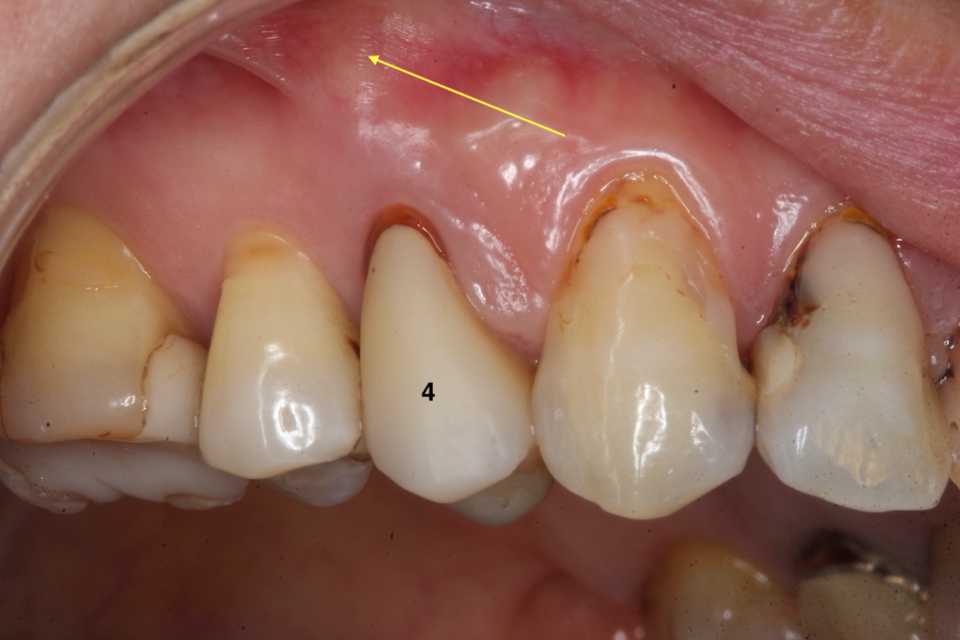

40代女性、右上4、Per+GAPerというのは根管治療後に根管内に感染を起こしている状態でGAとは炎症が根管の外に波及している状態。この方は10年程前に神経を取って被せたということでしたが、2、3年前GAができて別の歯医者に行ったら切って膿を出してもらったら治ったということでしたが、根管に細菌が感染している以上細菌が消えたりしないので、何度も再発します。今回は切開というよりは根管内部に3MIX+α-TCPを入れて根管内部を消毒殺菌しようというコンセプト。内部のポストも根管充填材も完全に除去する必要はない。根管充填材が見えるところまで穴を開けて薬剤を入れ、CRで蓋をするだけでよい。信じられないだろうが、これだけで治る。もし再発するようなら、冠のどこかに隙間があり、そこから細菌が出たり入ったりしているわけだから、冠もポストも除去して隙間を塞ぐ必要がある。多分従来の根幹治療しか知らない歯科医師は何が起こっているのか分からないと思うが、根管治療の真実が分かれば理解できないことはないと思う。一般に思われてる根管治療というのは理想からは程遠いものだということだ。冠にもポストにも根管充填材にも隙間だらけで細菌がその隙間から出入りしているのが現実だ。

では時系列でどうぞ